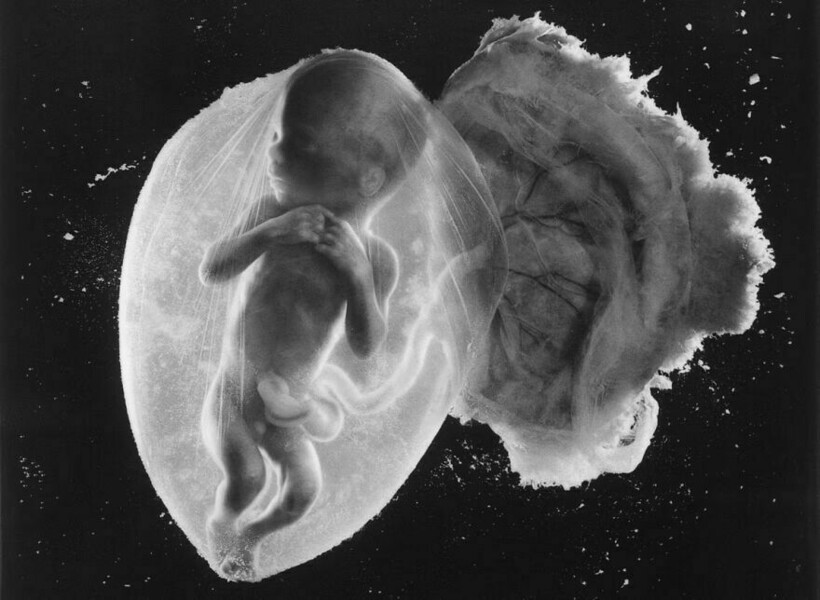

Леннарт Нильссон стал настоящей легендой фотографии, ведь он сделал то, чего не удавалось никому: показал миру, как развивается ребенок в утробе матери. Его проект «Ребенок родился» был создан в 1960-х годах, и он представляет собой детальные снимки эмбрионов на разных стадиях развития. Фотографии стали сенсационными, впервые они появились в журнале LIFE, и одна из них украсила обложку. На протяжении многих лет эти снимки публиковали в разных журналах.

Однако Леннарт с середины ХХ века увлекался микроскопией

А позже он экспериментировал с новыми методами фотографирования

Фотограф снимал детей в утробе матерей во время медицинских процедур

Он присутствовал на амниоцентезе и лапароскопии

Нильссон не скрывал, что снимал и эмбрионы после выкидышей и абортов

Почти все эти снимки сделаны в 1965 году, однако Нильссон фотографировал до конца своей жизни, и запечатлел не только развитие эмбриона, но и само зарождение жизни: вот тут мы собрали другие его фотографии.